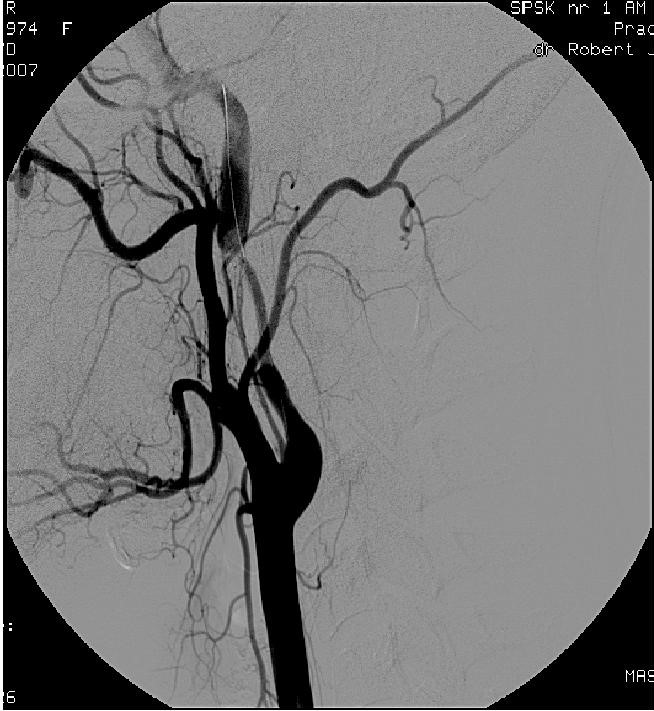

Na przedstawionej angiografii widoczne jest pourazowe objawowe zwężenie (krwiak śródścienny w obrębie tętnicy szyjnej wewnętrznej) u 55-letniej chorej. Najbardziej odpowiednią metodą leczenia jest: